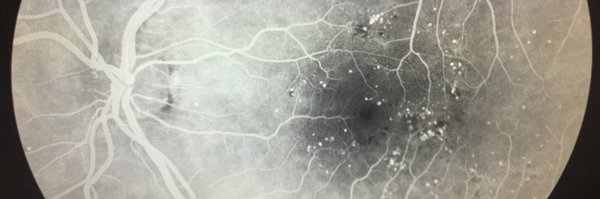

Wills Retina Drs. @JuliaHallerMD and Sunir Garg discuss #ChiefsRounds case of polypoidal choroidal vasculopathy (#PCV), a subtype of age-related #MacularDegeneration #AMDAwarenessMonth.